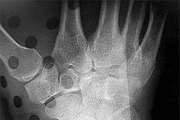

A 65-year-old active female presents to the emergency department after a mechanical fall. She complains of severe right groin pain and inability to bear weight. A representative radiograph of her injury is shown below. Assuming the image demonstrates a displaced (Garden IV) femoral neck fracture, which of the following is the most appropriate surgical intervention to maximize her functional outcome and minimize her lifetime revision rate?

Options:

Correct Answer: Total hip arthroplasty

For active, physiologically young older adults (typically 65-75 years old) with displaced femoral neck fractures, Total Hip Arthroplasty (THA) is the treatment of choice. Multiple randomized controlled trials have demonstrated that THA yields better long-term functional outcomes (e.g., higher Harris Hip Scores) and lower reoperation rates compared to hemiarthroplasty. Hemiarthroplasty (unipolar or bipolar) is generally reserved for lower-demand, older, or cognitively impaired patients. Internal fixation with cannulated screws for a Garden IV fracture in this age group carries an unacceptably high risk of nonunion and avascular necrosis.